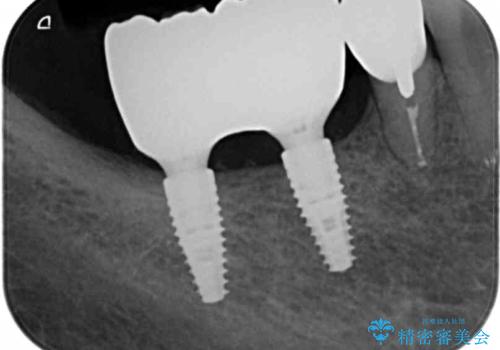

骨は薄くなってしまい、インプラントの長期的な安定を見込むには不十分でしたのでインプラントの埋入と同時に周囲にコツの造成を行う治療計画を立てます。

- 81.4万円 (straumann社製インプラント×2 アバットメント×2 仮歯×2 骨造成 ジルコニアクラウン×2)費用は治療当時の料金となります